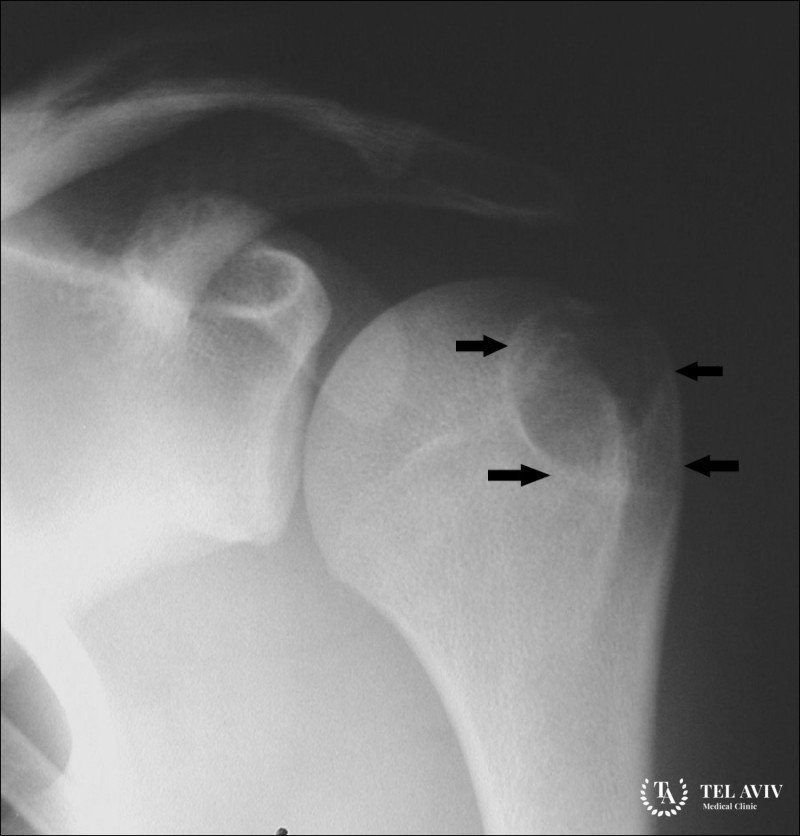

- Рентгенография – визуализируется в виде зоны просветления с неразмытыми границами, с гладкими или дольчатыми краями и тонким склеротическим ободком по периферии.